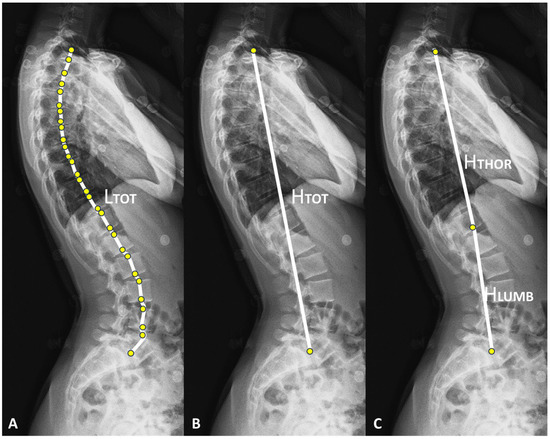

| Parameters (Unit) | Abbreviation | Definition |

|---|---|---|

| Length of the thoracolumbar spine (mm) | LTOT | Length of the broken line crossing each center of vertebral endplates from the cranial endplate of the first thoracic vertebra (T1) to the caudal endplate of the fifth lumbar vertebra (L5). |

| Thoracolumbar spine height (mm) | HTOT | Distance between the centers of the cranial endplate of first thoracic vertebra (T1) and the caudal endplate of fifth lumbar vertebra (L5). |

| Thoracic spine height (mm) | HTHOR | Distance between the centers of the cranial endplate of the first thoracic vertebra (T1) and the caudal endplate of the twelfth thoracic vertebra (T12). |

| Lumbar spine height (mm) | HLUMB | Distance between the centers of the caudal endplate of twelfth thoracic vertebra (T12) and the caudal endplate of the fifth lumbar vertebra (L5). |